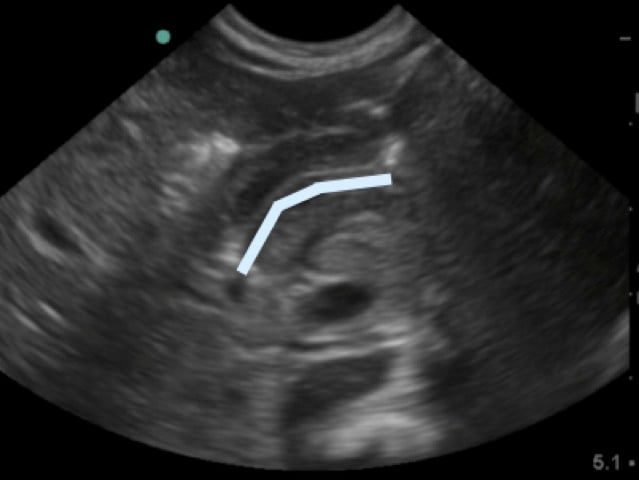

- In between the pyloric muscles is the hyperechoic pyloric channel made up of gastric mucosa.

- Figure 4b.Highlighted pyloric channel made up of gastric mucosa